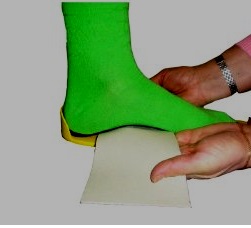

Branț prefabricate Special încălzit uscător când branț bază din plastic de căldură devine moale (plastic), branț este plasat sub picior.

Cum este modelarea suport plantar? Foarte simplu: cu ajutorul unei benzi de cauciuc trăgând arcul longitudinal al ascensorului picior la înălțimea fiziologic și amprenta meniurile metatarsian formează arc transversal a piciorului. Manipularea dureaza 1 minut. Identic pentru a oferi o simulare a branțului pentru piciorul opus.